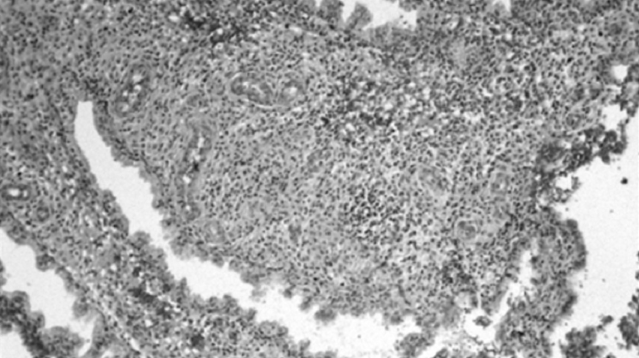

Analysis of IHC results revealed the presence of chronic endometritis with and without an autoimmune component. In terms of the receptor status of the endometrium in infertile women, chronic endometritis was accompanied by a decrease in ER expression in the glands in both the proliferative and secretory phases, but was mainly in the secretory phase in the stroma (Figure 1). PR expression in the glands and endometrial stroma decreases in the secretory phase (Figure 2).

Fig. 2. Progesterone receptors